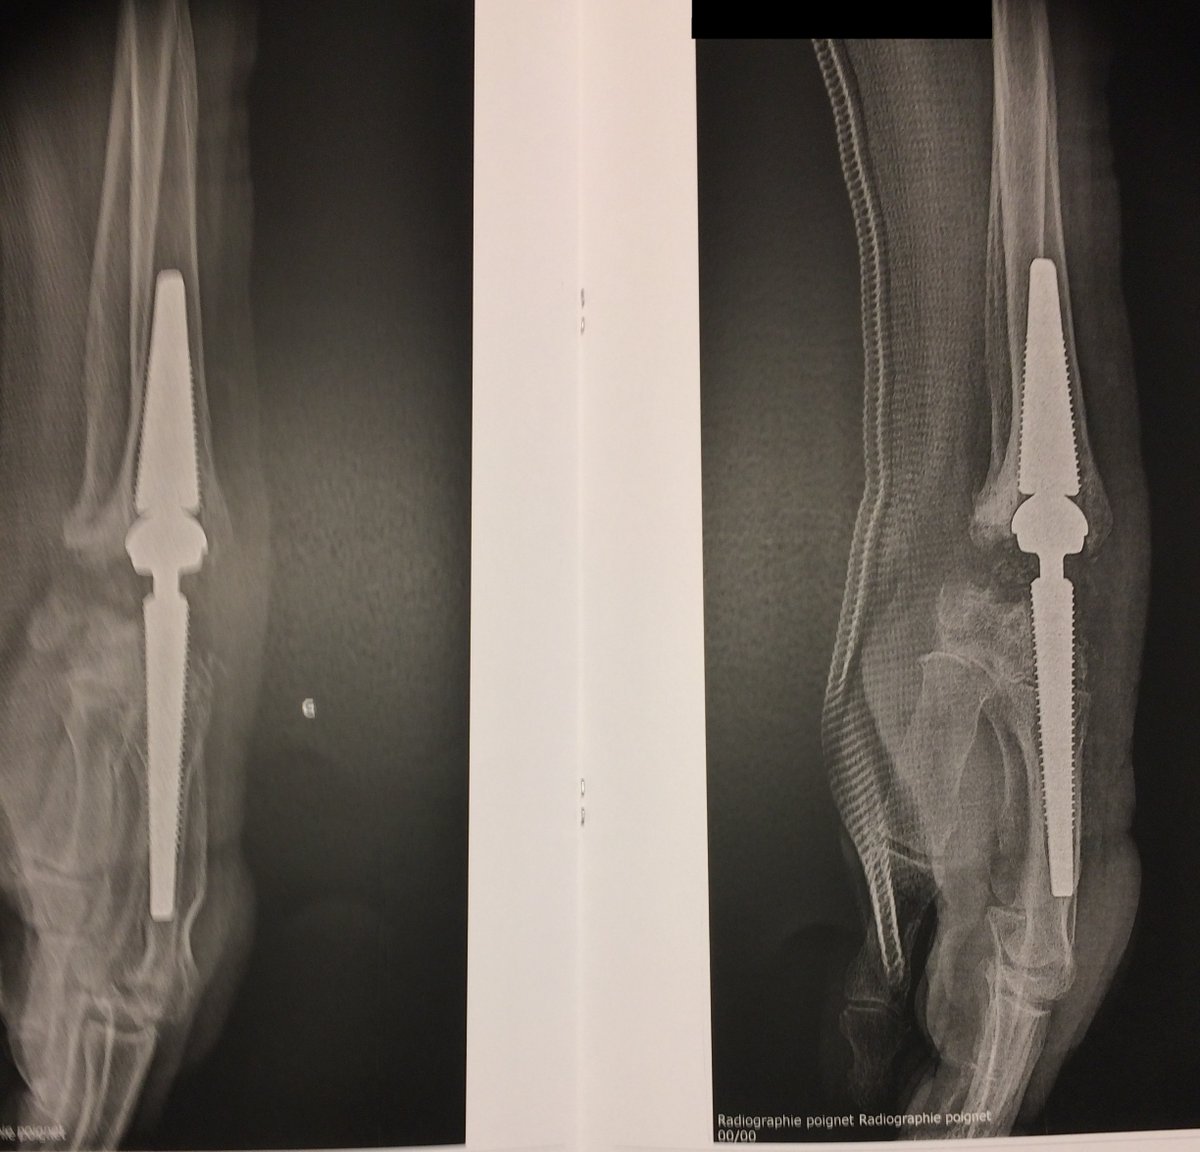

Chirurgien @CHUnantes / Institut de la Main 🦾 chirurgie du membre supérieur et de la main. Traumatologie générale 🦴 Vice président du @CJOjeunesorthos